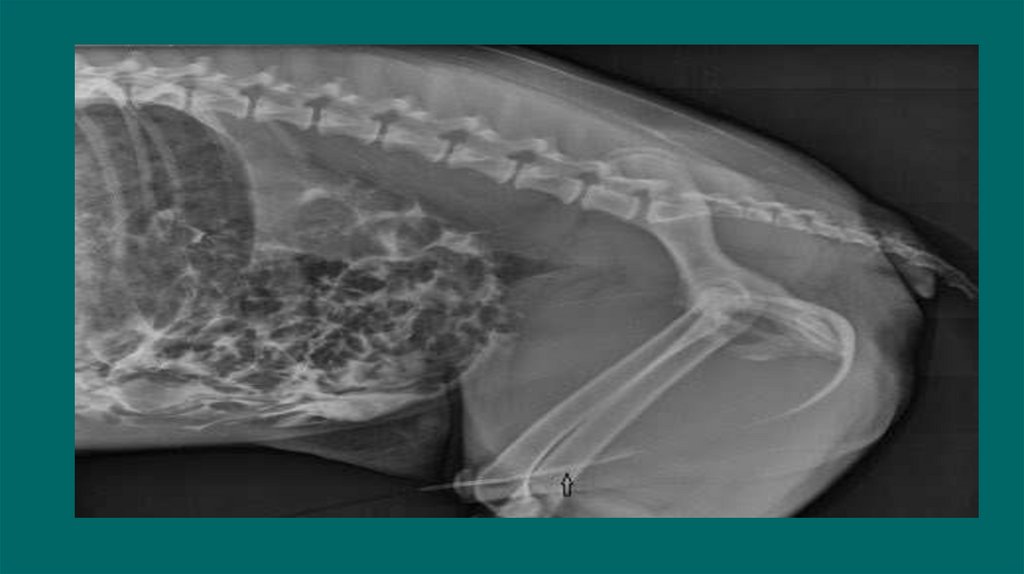

6. Рентгенологические исследования

Размер и симметричность почек, размер и топографию мочевого пузыря, размер и

положение репродуктивных органов.

У собак почки имеют бобовидную форму. Размер в 2,5-3,5 раза превышают длину L 2

У кошек овальная до круглой. Размер почек измеряют на ВД проекции в 2,4-3,0 раза

превышают длину L2

Размер проксимального отдела мочеточника :

Собаки 2-3мм. Кошки 1-2мм

Метод выявления рентгеноконтрастных уролитов (фосфат кальция, оксалат кальция,

струвиты)

Ураты /цистеиновые уролиты рентгенопрозрачны.

13. Позитивно-контрастная цистоуретрограмма

Показания:

Определение размера, формы и расположения мочевого пузыря

Определение проходимости или разрыва мочевого пузыря или уретры.

Обнаружение дефектов наполнения, связанных с уролитами (цистины/ураты) или гематомами,

выявления полипов или новообразований.